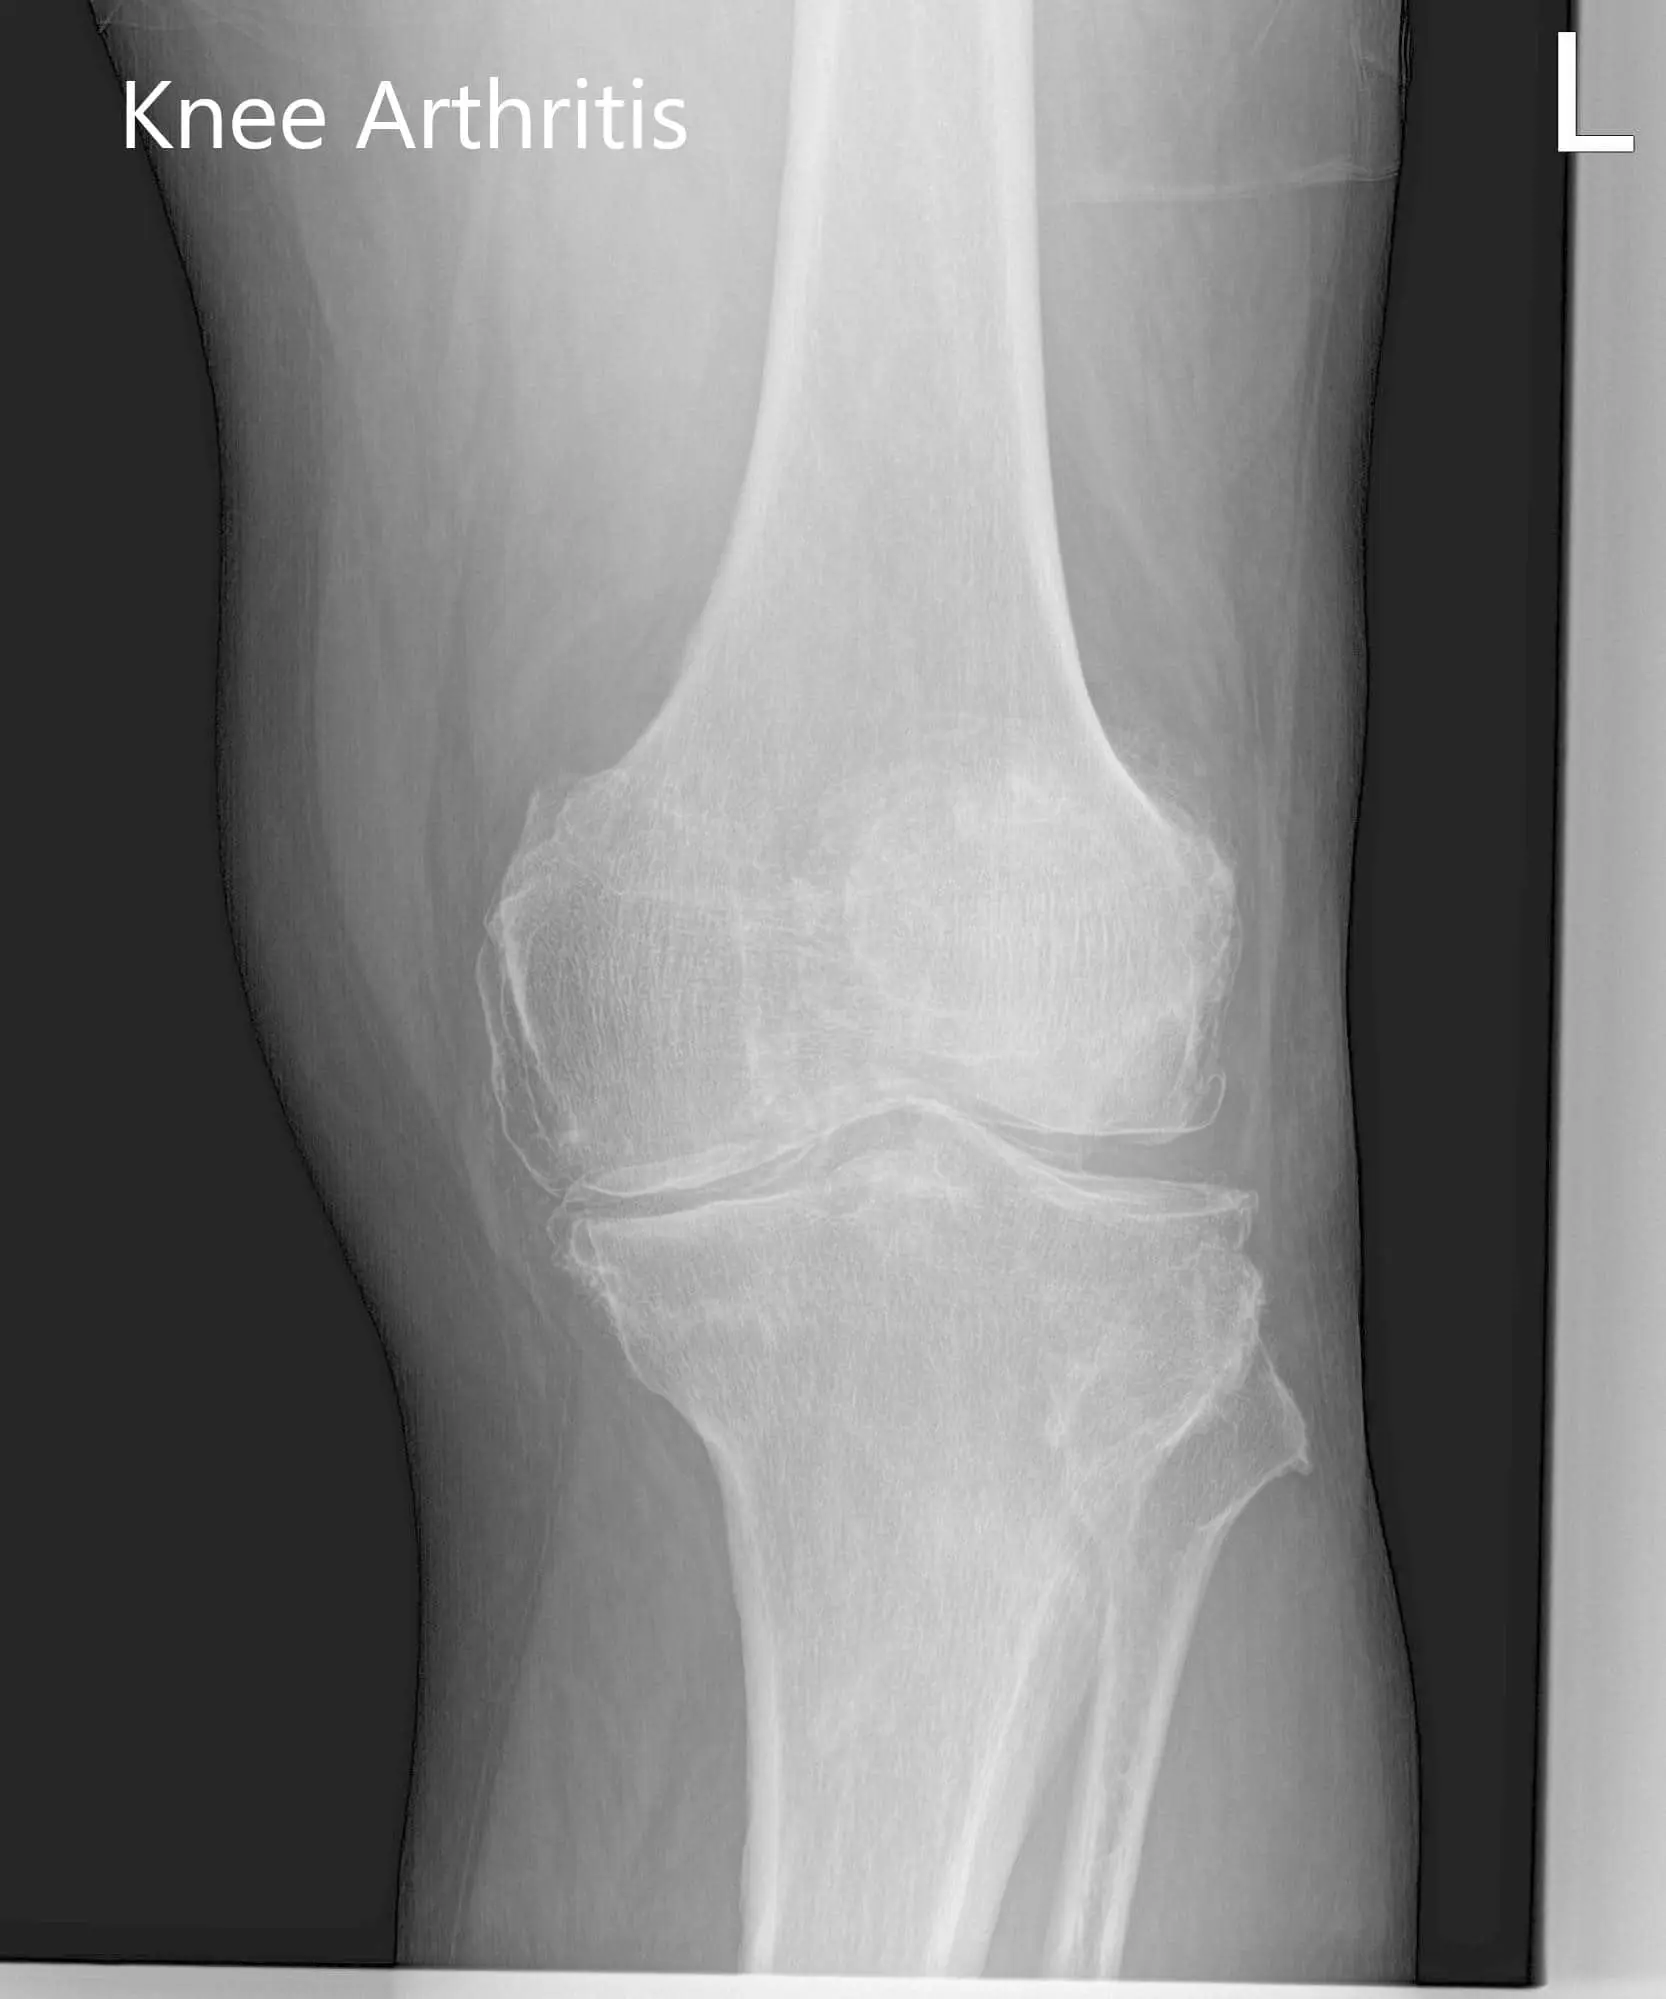

Considering his lifestyle limiting knee pain, various management options including both surgical and nonsurgical were discussed with him at length. He was considered a candidate for custom left knee total replacement. Risks, benefits and potential complications were discussed with him in detail. He agreed to the plan. Imaging studies revealed severe tricompartmental osteoarthritis of the left knee joint.

Preoperative X-ray of the left knee showing AP and lateral view of the knee with a skyline view of the patellaPreoperative X-ray of the left knee showing AP and lateral view of the knee with a skyline view of the patella - img 2Preoperative X-ray of the left knee showing AP and lateral view of the knee with a skyline view of the patella - img 3

Preoperative X-ray of the left knee showing AP and lateral view of the knee with a skyline view of the patella.